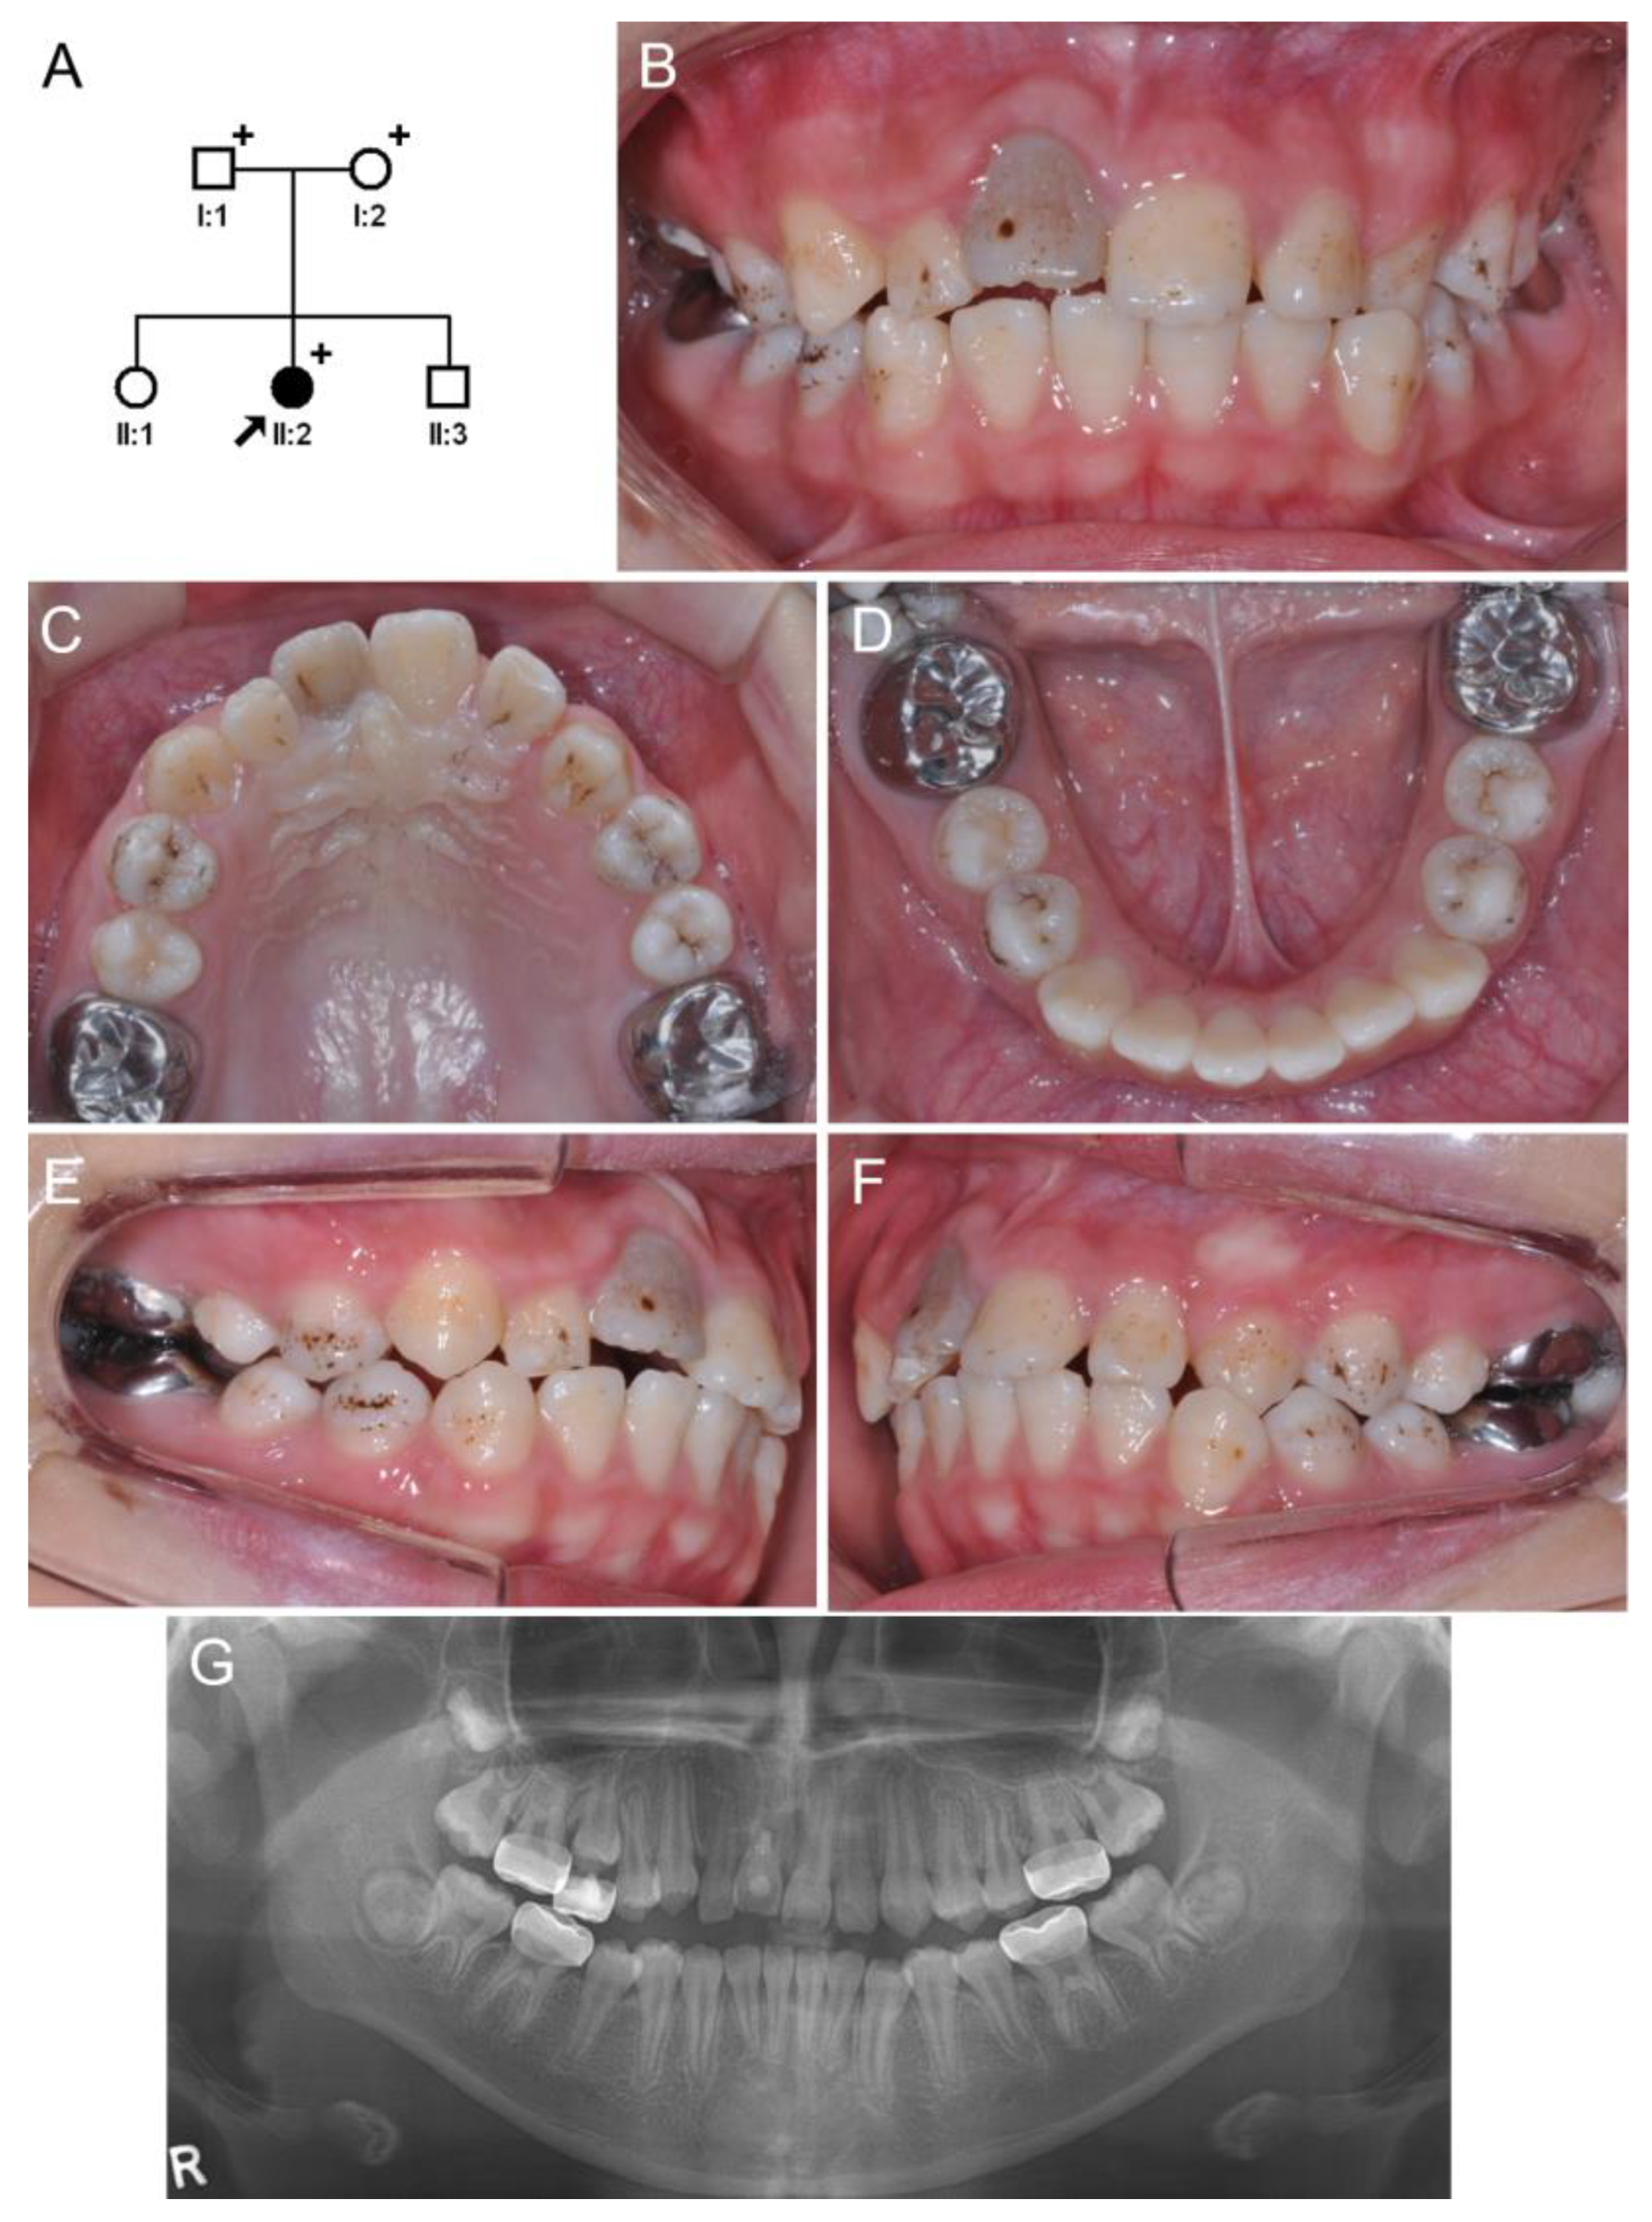

3.1. Family 1